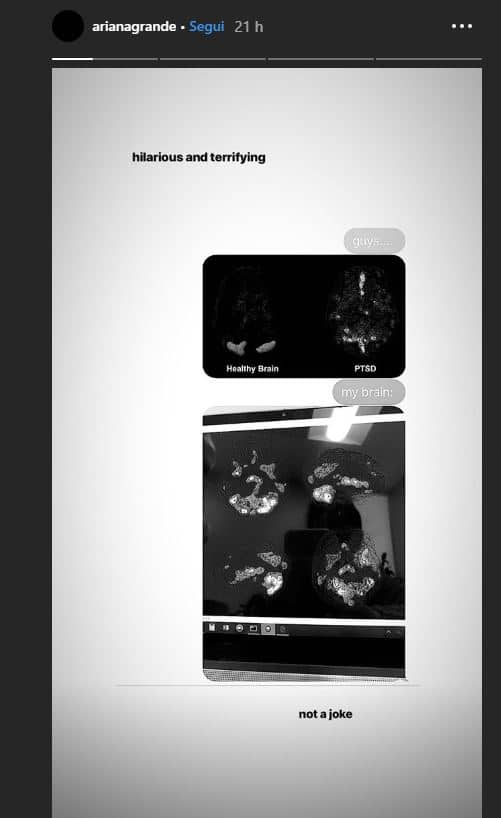

La popstar Ariana Grande ha pubblicato su Instagram la radiografia del suo cervello affetto da disturbo da stress post-traumatico (PTSD). La cantante e attrice americana soffre di questa patologia dal 2017 quando si trovò coinvolta in un attentato terroristico alla Manchester Arena proprio durante un suo concerto.

La Grande ha accompagnato alla foto il commento: “Not a joke”, non è uno scherzo. Già in passato la 25enne della Florida aveva spiegato ai suoi fan del trauma subito:”Tutti miei fan, le famiglie coinvolte, tutte le persone che erano lì ne hanno sofferto. Il tempo è la cosa più importante.